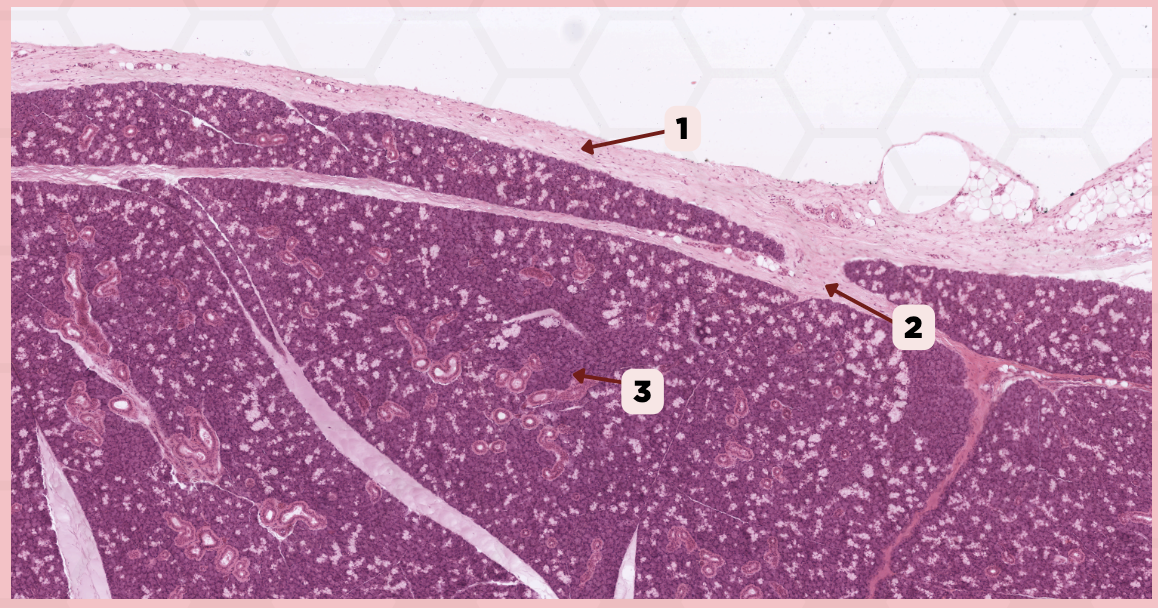

Submandibular

Identify the specimen.

Capsule

Identify the structure labeled as 1.

Septa

Identify the structure labeled as 2.